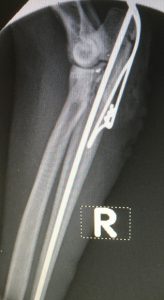

This right articular proximal ulna fracture occurred outside of the house in unknown circumstances about a week before the presentation.

It was reduced and fixed with a pin and tension wire and healed uneventfully. Sometimes we need to remove the implants in these cases after the fracture has healed.